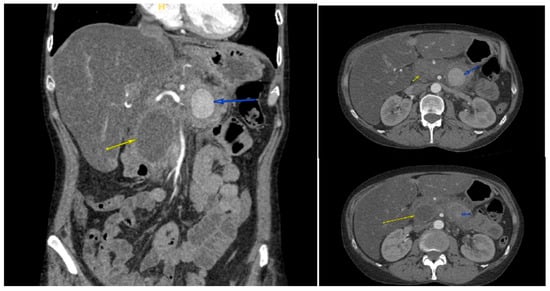

A 47-year-old female with a remarkable history of alcohol-induced chronic pancreatitis and alcohol use disorder presented in June 2024 with symptoms including hematochezia, melena, and syncope. Upon her admission, she showed signs of low blood pressure and tachycardia. The results of laboratory tests showed a hemoglobin level of 7.1 g/dL and a serum lipase of 449 U/L. Given the patient’s hemodynamic instability and history of chronic pancreatitis, CT angiography (CTA) was performed urgently instead of initial esophagogastroduodenoscopy (EGD) to rule out vascular complications, revealing a 3.6 × 3.7 × 3.5 cm pseudoaneurysm developing from the splenic artery at the junction of the pancreatic body and tail (Figure 1), next to a 4.2 cm pancreatic head pseudocyst (Figure 2). The bleed was presumed to involve fistulization into the GI tract, potentially via the pancreatic duct (virsungorrhagia), though not directly visualized on initial or follow-up imaging.

Figure 1. Contrast-enhanced CT angiography of the abdomen showed a 3.5 cm pseudoaneurysm developing from the splenic artery at the junction of the pancreatic body and tail (arrows) next to a 5.4 cm pancreatic head pseudocyst (no arrows).

Figure 2. Contrast-enhanced CT angiography of the abdomen showed a 3.6 × 3.7 × 3.5 cm pseudoaneurysm (blue arrows), next to a 4.2 cm pancreatic head pseudocyst (yellow arrows).